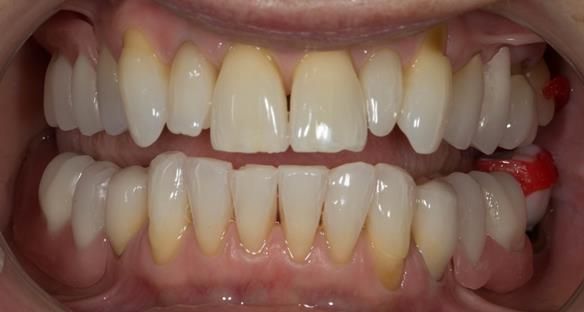

This newsletter describes in step by step detail Angela's transition through immediate partial dentures to crown supported definitive metal based dentures.

This 58 year old woman was referred to me by her general dental practitoner for treatment.

- Generalised Periodontitis; Stage 4, Grade C, Currently Unstable. Risk Factors: Type 1 diabetes. 16, 17 - hopeless prognosis. 14, 24, 26, 27, 34, 37, 44 - guarded prognosis

- Poor marginal fit and poor appearance of crowns and bridgework

- Yellowing teeth

The clinical situation and treatment process is shown in detail below with photographs. I (Finlay Sutton) provided the clinical work and Rowan Garstang provided the technical work.